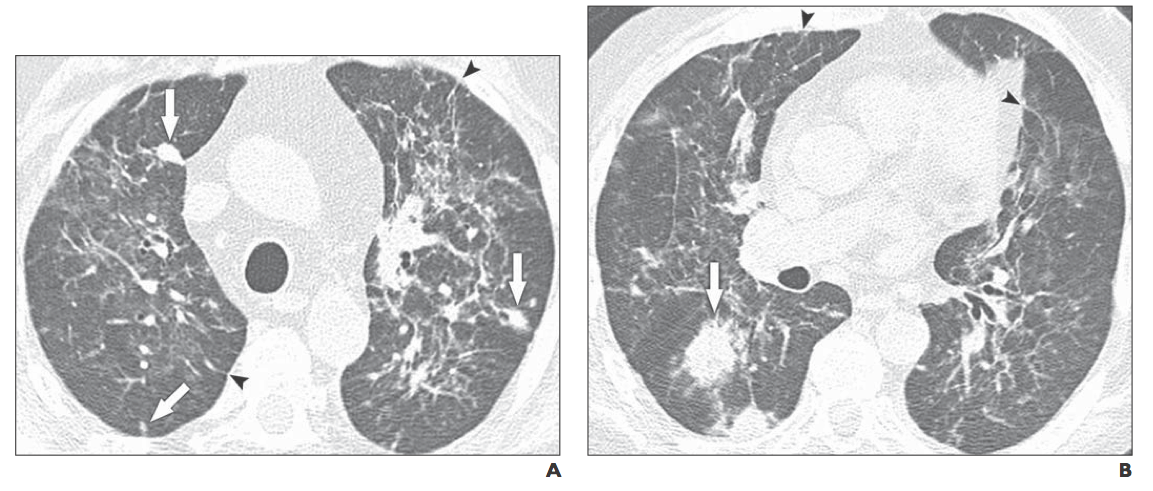

PCPとCMV肺炎の画像の比較

31例のCMV肺炎と27例のPCP症例を比較

(Br J Radiol. 2007 Jul;80(955):516-23. Abstruct)

・CMV肺炎は全例血液腫瘍を背景とし, 26例は造血幹細胞移植後の発症

・PCPは血液腫瘍は17例, 造血幹細胞移植後は6例, 固型腫瘍5例, ステロイド 5例と背景疾患は様々.

CT所見では5種類の所見に有意差が認められた

・肺尖部の病変

モザイクパターン

均一なGGO所見 の3項目はPCPで有意に認められる所見,

・小結節病変

GGOやConsolidationの境界が不鮮明なのはCMV肺炎で有意に認められる

・末梢側のスペア, Consoliation, 小葉間隔壁肥厚は両者で同等

21例のCMV肺炎, 70例のPCP症例の画像所見を比較

(Acta Radiol. 2015 Jul;56(7):806-13. Abstruct)

・CMV肺炎で有意に多く認められる所見は,

小結節像, Tree-in-budパターン, Haloサインの3つ

・PCPでは広い範囲のGGO, モザイクパターン, びまん性分布が有意に多い